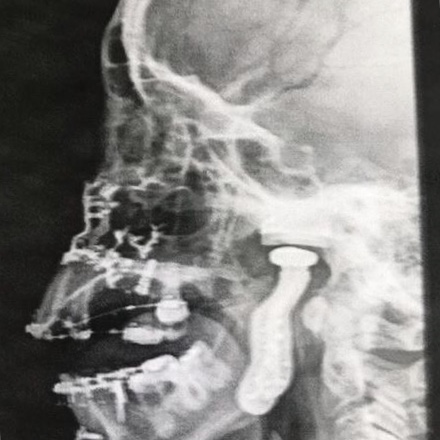

No começo durou 4 meses, já estávamos em 2017, fiz 3 infiltrações porque as 2 anteriores não fizeram o efeito necessário. Até que Deus iluminou meu caminho e a Patricia Zelante Veras compartilhou a história dela. Eu voei do MT (Mato Grosso) para São Paulo e fui consultar com o Dr Roberto Piteri, já era novembro de 2017. Esses anjos de Deus me ajudaram muito. O plano demorou a liberar e não cobria a equipe porque não eram médicos mas uma especialidade da odontologia. Diagnóstico: reabsorção dos côndilos mandibulares, uma degeneração bilateralmente.

A dor já estava absurda e eu não tinha mais vida. O que acelerou mais ainda o processo foi o queixo pequeno demais. Era operar ou operar. Eu alternava entre codeína, tramal e morfina. Meu fígado e meu estômago ficaram arrebentados e eu já estava psicótica de tanto analgésico. Finalmente, operei em 15/11/2018 depois de 2 anos de dor e lágrimas. Do momento em que acordei da anestesia até agora eu não tive mais dor na ATM. Nem acredito que hoje eu tomo umas gotinhas de dipirona apenas! Estou explodindo de felicidade.

Claro que não foi fácil porque a cirurgia foi super invasiva e eu senti as crises por ter que suspender os remédios da artrite para poder operar. Mas valeu muito à pena! Gente, muitos fazem artroplastia no quadril, ombro, joelhos, acrescentem a ATM na lista. E digo que não é plaquinha de bruxismo ou aparelho que resolvem. Precisamos de atendimento interdisciplinar e de profissionais que possam entender nossa condição.Quem precisar de ajuda pode contar comigo.